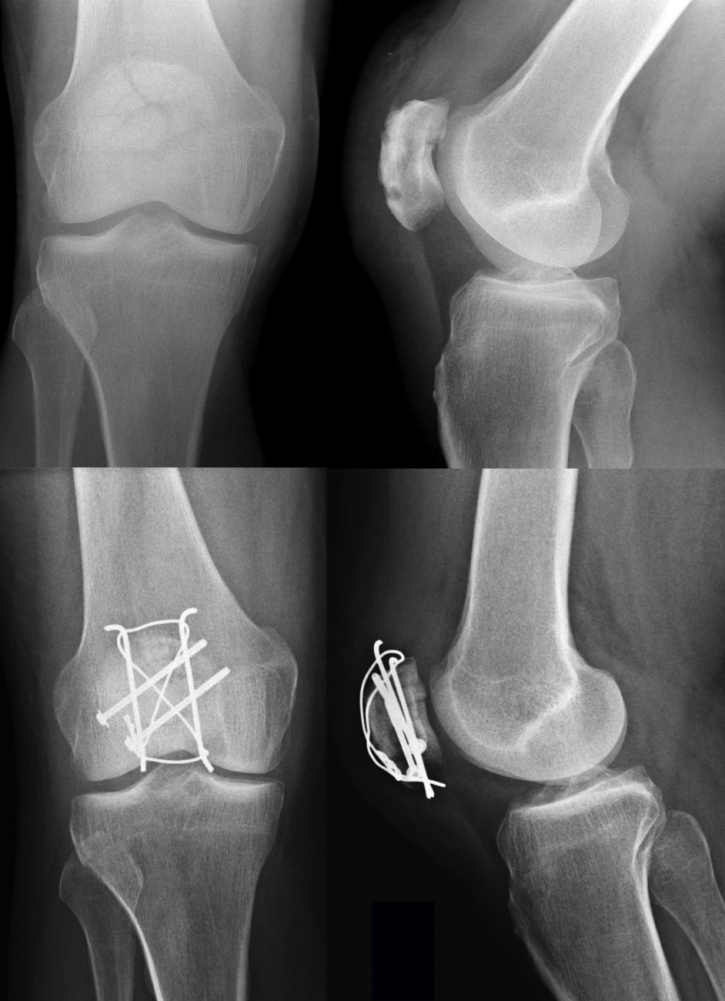

图3:髌骨粉碎性骨折术前X线片(上图)。术后3个月采用克氏针、螺钉联合“8”字形钢丝环扎固定(下图)